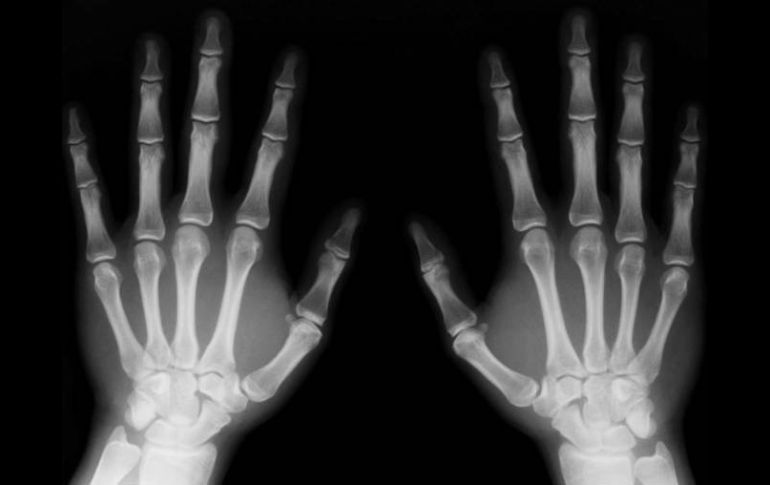

Según la investigación, la vitamina E destruye más hueso del que se crea. ESPECIAL  /

La cantidad de masa ósea está determinada por el equilibrio entre dos tipos de células: los osteoblastos, que intervienen en la creación del nuevo tejido óseo, y los osteoclastos, que lo degradan.

En la investigación japonesa, los ratones con dosis altas de vitamina E perdieron masa ósea, un dato que los científicos consideran que se debe a que este componente aumenta el número de osteoclastos, lo que a su vez se traduce en que se destruye más hueso del que se crea.